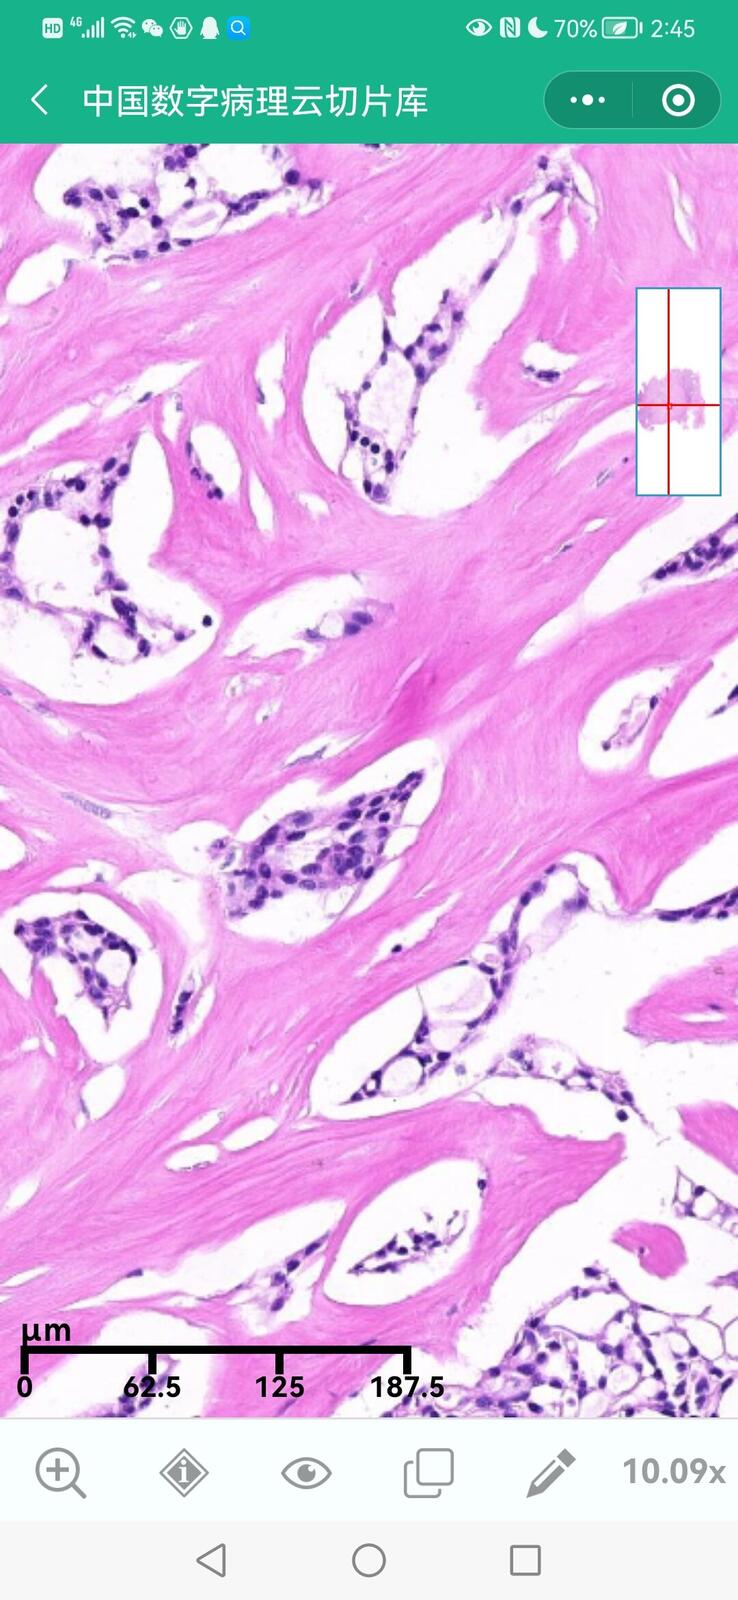

乳腺黏液性囊腺瘤伴导管内癌

乳腺多形性脂肪肉瘤

乳腺叶状囊肉瘤

乳腺分泌性癌(29岁)